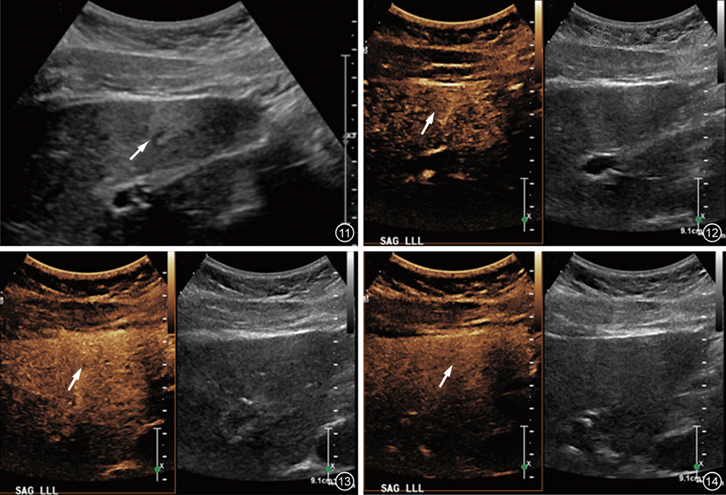

图11~14 患儿女性,14岁,肝左叶局灶性脂肪瘤灰阶超声及造影增强超声图像。图11灰阶声像图示肝左叶局灶性回声肿块(箭头所示);图12~14为造影增强超声(左)与灰阶超声(右)双幅对比图像,显示肿块(箭头所示)在动脉相(图12)、门脉相(图13)、静脉相(图14)与周围肝实质呈等增强